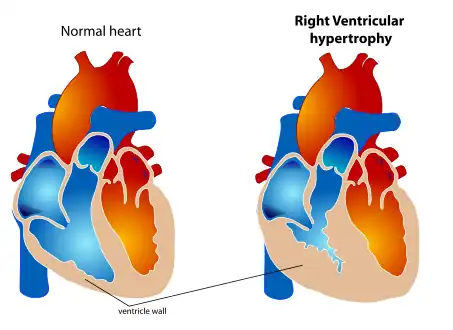

| Right ventricular hypertrophy | |

Pulmonary heart disease, also known as cor pulmonale, is the enlargement and failure of the right ventricle of the heart as a response to increased vascular resistance (such as from pulmonic stenosis) or high blood pressure in the lungs.[2]

Chronic pulmonary heart disease usually results in right ventricular hypertrophy (RVH),[4] whereas acute pulmonary heart disease usually results in dilatation.[5] Hypertrophy is an adaptive response to a long-term increase in pressure. Individual muscle cells grow larger (in thickness) and change to drive the increased contractile force required to move the blood against greater resistance. Dilatation is a stretching (in length) of the ventricle in response to acute increased pressure.[6]

a-d)2DE (two dimensional echocardiography) features of cor pulmonale Normal heart (left) and right ventricular hypertrophy

Normal heart (left) and right ventricular hypertrophy P pulmonale